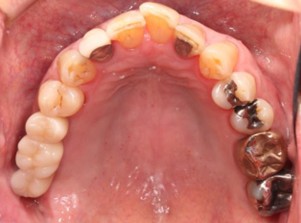

40代 女性

- リスク・副作用

- 術後疼痛、歯肉腫脹

- 治療の費用

- 合計¥686,000(税込)

【内訳】

インプラント(1本) ¥440,000

その他費用¥246,000

(薬・注射・レントゲン・CT・データ分析・骨造成・サージカルステント・血液検査) - 年齢/性別

- 40代/女性

- 患者の具体的な症状

- 左上6欠損のため義歯を使用していたが、噛むと痛みがあり不快なため、インプラント治療を希望

- 検査方法

- コーンビームCT、レントゲン撮影

- 診断結果

- 左下6欠損

- 治療詳細

- コーンビームCTによる画像診断で垂直的な骨高が不足し骨密度が少ないため、ソケットリフトによる骨再生治療とインプラント埋入を同時に行った。

- 通院回数

- 7回

- 治療期間

- 7か月